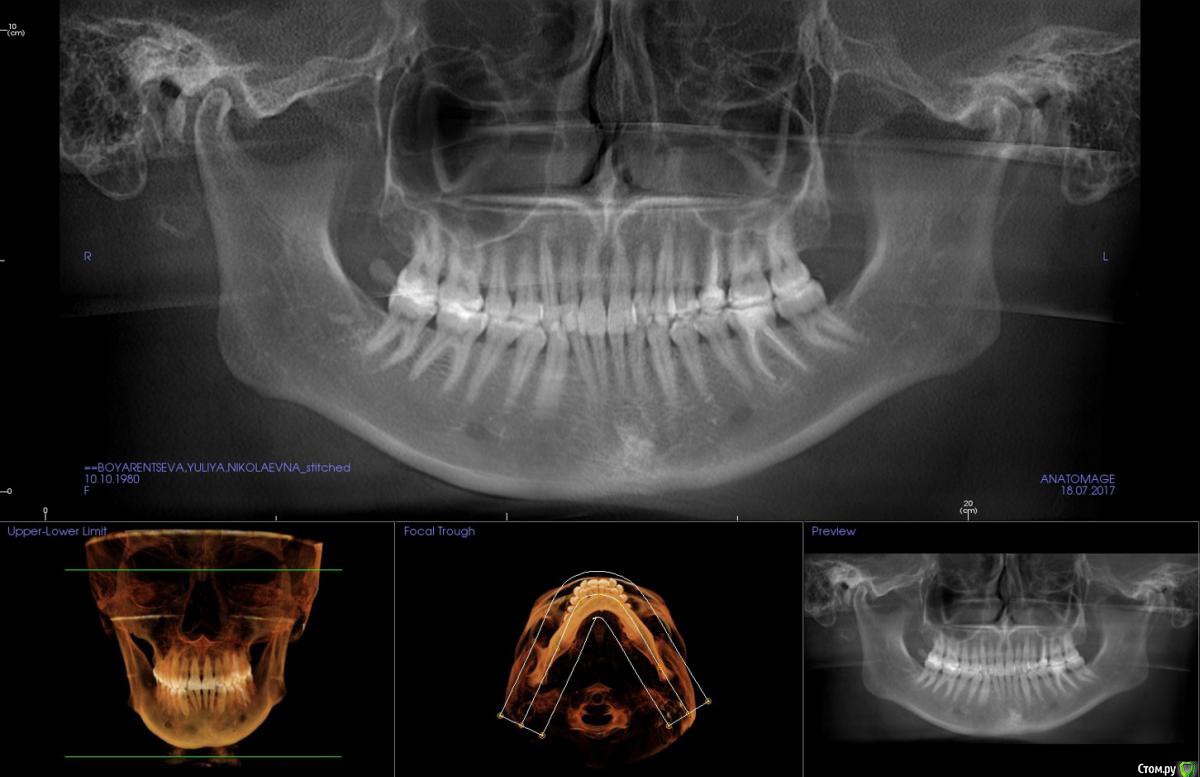

kapyulia Опубликовано 22 декабря, 2017 Поделиться Опубликовано 22 декабря, 2017 Добрый день! Могли бы Вы подсказать есть ли необходимость в удалении зубов (пятерки) с верхней челюсти? Спасибо за помощь. Ссылка на комментарий

Brigita Опубликовано 24 декабря, 2017 Поделиться Опубликовано 24 декабря, 2017 Сложно сказать без очного осмотра, по фото показаний нет. Ссылка на комментарий